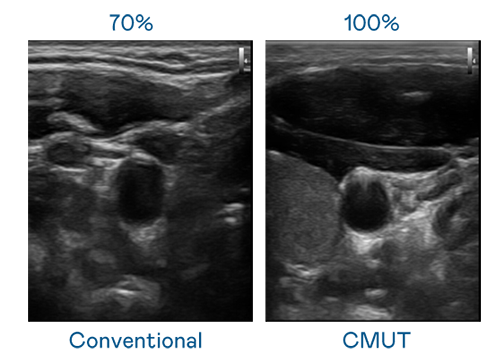

CMUT 技术是一种用电容式微机电元件来产生超音波讯号的技术。与传统 PZT 压电式技术相比,CMUT 频宽增加 30%,更宽频的超音波讯号让影像解析度大幅提升,是实现高影像品质医疗超音波扫描、促进精准医疗发展的关键技术。

超音波影像的解析度高低,首先取决于探头能发出的讯号频宽。EVO视讯 CMUT 可提供高清晰的超音波讯号,提供高频宽、高灵敏度、影像纹理细节更高的超音波影像,协助医护人员缩短影像判读时间及利用精准的医疗影像进行诊断。